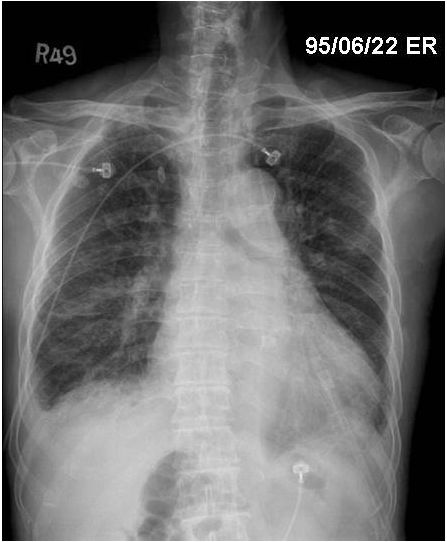

17. 60歲男性,患有糖尿病及肺氣腫,因嚴重社區型肺炎併發急性呼吸窘迫症候群及呼吸衰竭插管住進加護病房。住院十天後,情況逐漸穩定,但偶爾會躁動及咳嗽。體溫 37.5℃, 血壓 115/70 mmHg, 心速率 90/min, 規則, 呼吸速率 22/min, SaO2 94% (使用 Fi O2 70% , pressure control mode, PEEP 14 cm H2O, plateau pressure 34 cm H2O)。隔日早上護士小姐緊急通知病人突然意識喪失,四肢發紺,血壓60/30 mmHg , 心跳突然增快到150/min : 體溫38℃, 呼吸速率35/min, 呼吸音微弱,呼吸器呈現 high pressure alarm, 即使以ambu bagging 也很難將氧氣送入。此病人之休克最有可能是下列哪一種?

(A) 肺動脈栓塞併阻塞性休克。 (B) 心肌梗塞併心因性休克。 (C) 肺炎惡化併敗血性休克。 (D) 張力性氣胸併阻塞性休克。 (E) 心室上頻脈併心因性休克。